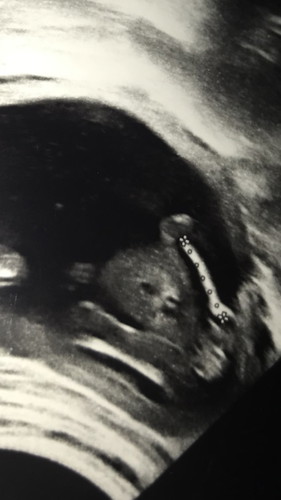

แม่ๆคะใบหน้าและปากน้องปกติมั้ยคะ

ตอน17วีคนะคะรูปซาว

หมอได้บอกไหมค่ะว่าปกติ